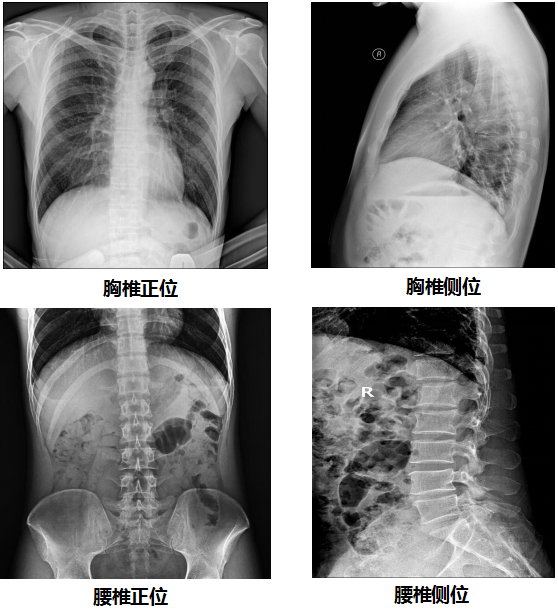

【PLD7300系列雙立柱DR臨床圖像】